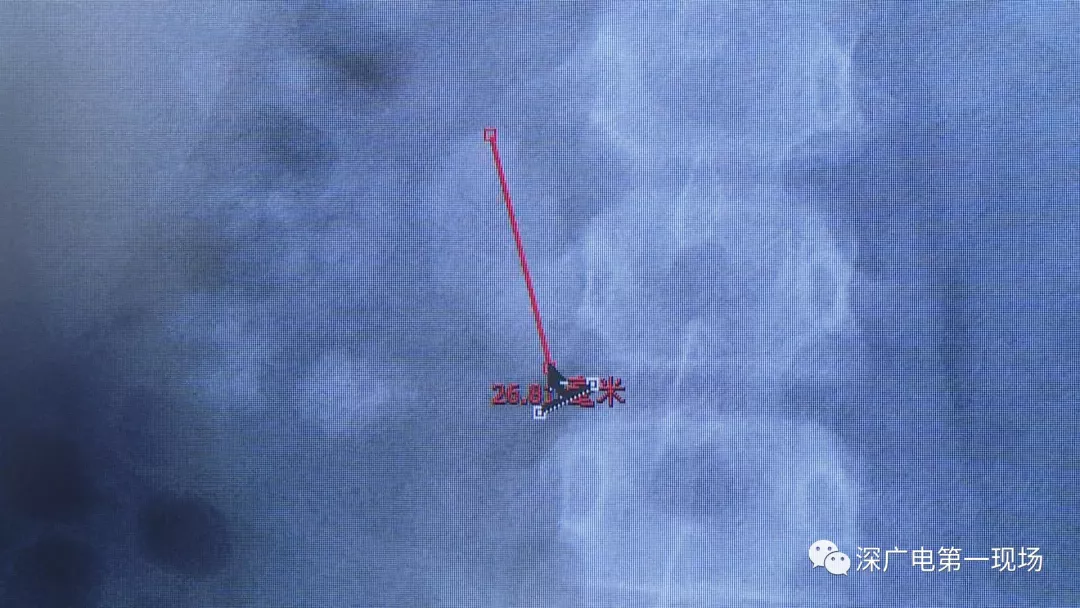

小軒這種情況,其中,最大的結石長約2.7厘米,寬約1.7厘米,體積堪比鵪鶉蛋,不但造成了尿路堵塞,還導致了右腎中度積水。